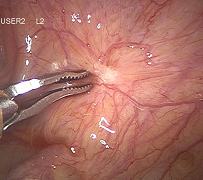

Hysteroskopische Myomresektion

Myome, die sich in der Gebärmutterhöhle befinden oder direkt unter der Gebärmutterschleimhaut (Endometrium) liegen, werden als intracavitäre bzw. submuköse Myome bezeichnet. Sie verursachen typischerweise Blutungsstörungen, z. B. in Form übermäßig starker und verlängerter Menstruationsblutungen. Diese können zu einer Blutarmut (Anämie) und zu einem Eisenmangel führen. Müdigkeit, Abgeschlagenheit und eine reduzierte Belastbarkeit sind häufig die Folgen.

Im Zusammenhang mit einer geplanten Schwangerschaft können intracavitäre und submuköse Myome unter Umständen die Entstehung einer Schwangerschaft behindern oder aber für Fehl- und Frühgeburten verantwortlich sein. Diese Myome können heutzutage häufig durch eine Gebärmutterspiegelung, eine sogenannte hysteroskopische Operation, entfernt werden. Dabei wird ein stabartiges optisches Instrument, das Hysteroskop, das einen Durchmesser von nur wenigen Millimetern aufweist, durch die Scheide und den Muttermund in die Gebärmutter eingeführt. Eine im Schaft des Hysteroskops befindliche elektrische Schlinge ermöglicht es, Myome schichtweise abzutragen. Die Gebärmutterhöhle wird dabei durch eine Flüssigkeit entfaltet.

Hysteroskopische Operationen sind technisch aufwändige Verfahren, die je nach Größe und Lage der zu entfernenden Myome eine entsprechende Erfahrung des Operateurs erfordern. Unter Umständen ist eine medikamentöse Vorbehandlung sinnvoll, da hierdurch Myome vor der Operation verkleinert werden können, so dass die Operation danach schneller und sicherer durchzuführen ist.

Durch die hysteroskopische Entfernung von Myomen können Blutungsstörungen beseitigt, Schwangerschaften ermöglicht und häufig größere Operationen wie z. B. die Entfernung der Gebärmutter (Hysterektomie) vermieden werden. Weitere Vorteile sind die nur geringen operationsbedingten Beschwerden sowie die schnelle Erholungsphase. Weitere Details, Behandlungsalternativen sowie die mit einer hysteroskopischen Operation verbundenen Risiken besprechen wir gerne mit Ihnen in einem persönlichen Gespräch.